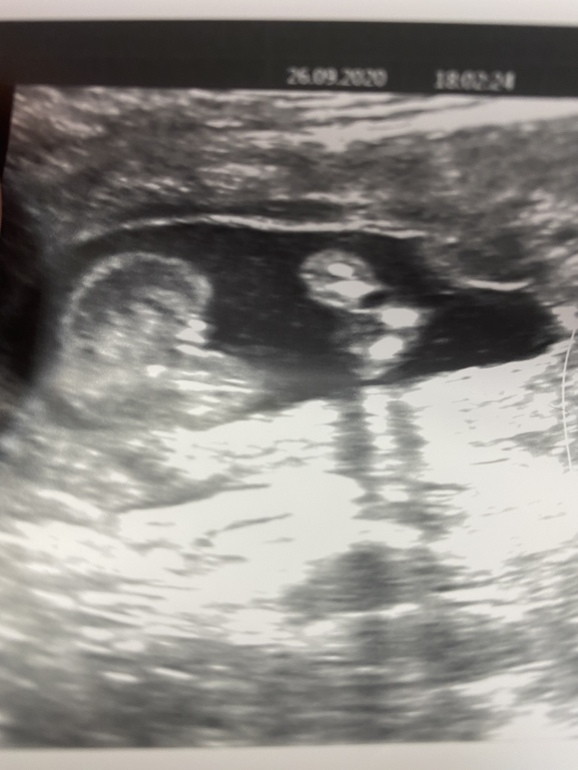

Сначала пообещали девочку, потом мальчика( фото прилагаю, но я думаю, что врач ошиблась), а сегодня малыш прятался и точно пол не сказали

Я, честно говоря, думала, что в Санкт-Петербурге такое вообще невозможно. Аппарат УЗИ хороший. Врач с опытом. Вот так и ошибаются с полом.

Да видно что аппарат хороший по снимку,я не так давно пост выкладывала там девушка выкладывала похожее фото и писала что по узи была девочка а родился мальчик вот так бывает..)